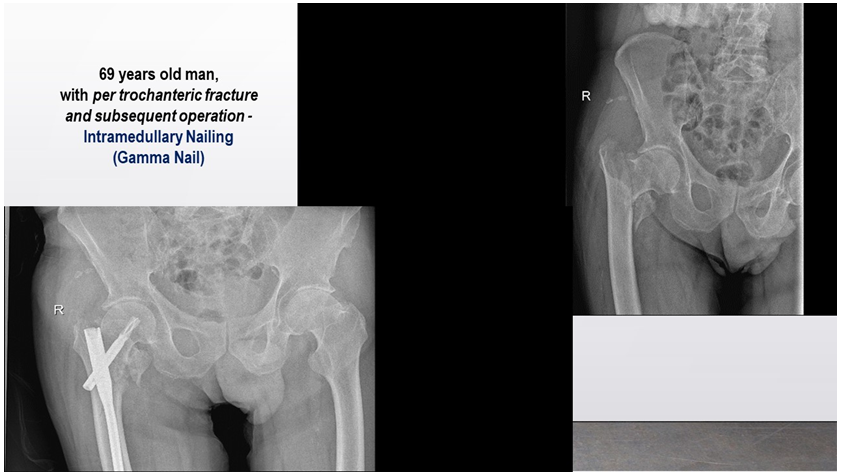

In geriatric rehabilitation, major goals are the improvement of the range of motion (ROM) of the hip, verticalization of the patient and gait training with gradual Weight-Bearing (WB – from 0% to 100%). Next figures (Figures 6–12) present data of some of our in-patients (X-ray) at the admission in the orthopaedic department (Figure 6) and / or in our PRM-Department (Figures 7–12). We proceed the rehabilitation of different type of patients: with Intertrochanteric fractures and subsequent hip replacement (Figure 6,7), with metallic osteosynthesis of the femoral body after a peri-prosthetic fracture (previous hip replacement) (Figure 8), with hip re-arthroplasty after a periprostheticdiaphyseal femoral fracture (Figure 9), with inter-trochanteric fracture and subsequent orthopedic surgery – intramedullary nailing (Figure 10), with per-trochanteric fracture, operated with implantation of metallic osteosynthesis – PCOM with DHS plaque (Figure 11), with proximal diaphyseal femoral fracture with dislocation and intervention of PCOM with DHS plaque (Figure 12).

Figure 10 Patient with inter-trochanteric fracture and subsequent orthopedic surgery – intramedullary nailing.